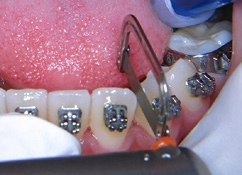

Die Arbeitsschritte sind Folgende: Mit dem Opener-Strip wird der erste Kontaktpunkt entfernt und somit entsteht der Spalt zwischen den benachbarten Zähnen, die zu strippen sind (Abb. 15). Mit dem nächsten Strip wird die Zahnhartsubstanz weiter abgetragen. Die Strips haben bei der Erstanwendung fest definierte Blattstärken, die aber naturgemäß nur bei der ersten Nutzung der Instrumente gegeben sind. Eine stete Prüfung des Spaltmaßes ist für jedes System erforderlich. Nach Öffnen des erforderlichen Spaltes zwischen den benachbarten Zähnen können die Strips am Rahmen mit den Daumen leicht gebogen bzw. gerundet werden; dadurch wird das diamantierte Band flexibler und kann die interdentale Eröffnung/Spalt konturieren und dem Zahn die natürliche Form zurückgeben (Abb. 16). Als letzter Schritt folgen die Politur mit dem Polierstreifen und die Applikation fluorhaltigen Materials (Abb. 17).

Für die Behandlung und geplanten Zahnbewegungen wurde eine festsitzende Apparatur (0,022 × 0,028 Slot-Brackets) eingegliedert; im Oberkiefer erfolgte eine vollständige Bebänderung, im Unterkiefer nur eine Teilbebänderung der Seitenzähne (Abb. 22a bis c). Aufgrund der Achsenstellung der Fronten im Unterkiefer sollte eine weitere labiale Kippung bei der Auflösung des Engstandes vermieden werden. Um dies weitestgehend umsetzen zu können, wurde im gesamten Frontzahngebiet und bei den seitlichen Zähnen inklusive der Mesialfläche der Unterkiefereckzähne um insgesamt 4 mm gestrippt (0,20 bis 0,25 je Approximalfläche). Die Form der Zähne und der Verlauf der Gingiva ließen dies zu. Zu Beginn der Behandlung wurden nur die 1. Molaren, Prämolaren und Eckzähne bebändert, um die Proklination der unteren Schneidezähne zu vermeiden. Die Prämolaren wurden jeweils von mesial und distal sowie die Eckzähne von distal mit dem oszillierenden EVA-Winkelstück mit Hubbewegung gestrippt. Für eine effektive Distalisation und Ausnutzung des gewonnenen Platzes wurde in den Bogen zwischen den Zähnen 33 und 43 eine Druckfeder eingesetzt (Abb. 23). Nach vollständiger Distalisation der seitlichen Zähne wurden die Schneidezähne beklebt. Vor dem Einligieren des Bogens wurde die Unterkieferfront von mesial und distal einschließlich der mesialen Fläche der Eckzähne gestrippt. Es wurden Lace-backs und voller Bogen eingesetzt (Abb. 24a bis c).